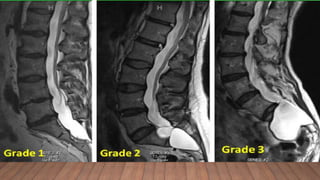

Dural ectasia

• Enlargement of the spinal canal owing to progressive ectasia of dura and neural

foramina and to erosion of vertebral bone.

• Usually involves the lumbosacral spine 60-90% pts on MRI/CT.

• It is sensitive but not specific sign of MFS, and is commonly seen in Loeys-Dietz

syndrome and Shprintzen-Goldberg syndrome, has been reported in the vascular form

of Ehlers-Danlos syndrome.

• MRI most sensitive technique.

• No correlation appears to exist between the severity of dural ectasia and the degree of aortic

dilatation.

• Lower spine CT scan or MRI can be performed to exclude dural ectasia.